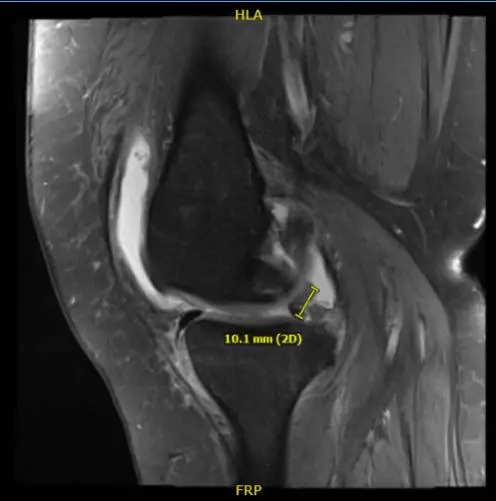

MRI result impression as follows: Bone marrow edema at the anterior peripheral aspect of the medial tibial plateau with slight flattening and irregularity of the articular surface there is a low-grade healing subchondral impaction or stress fracture.

Complex tear of the posterior horn medial meniscus including a displaced meniscal flap abutting the posterior root and measures 1 cm in length. Severe patellofemoral arthrosis. Moderate femorotibial arthrosis. Moderate joint effusion.